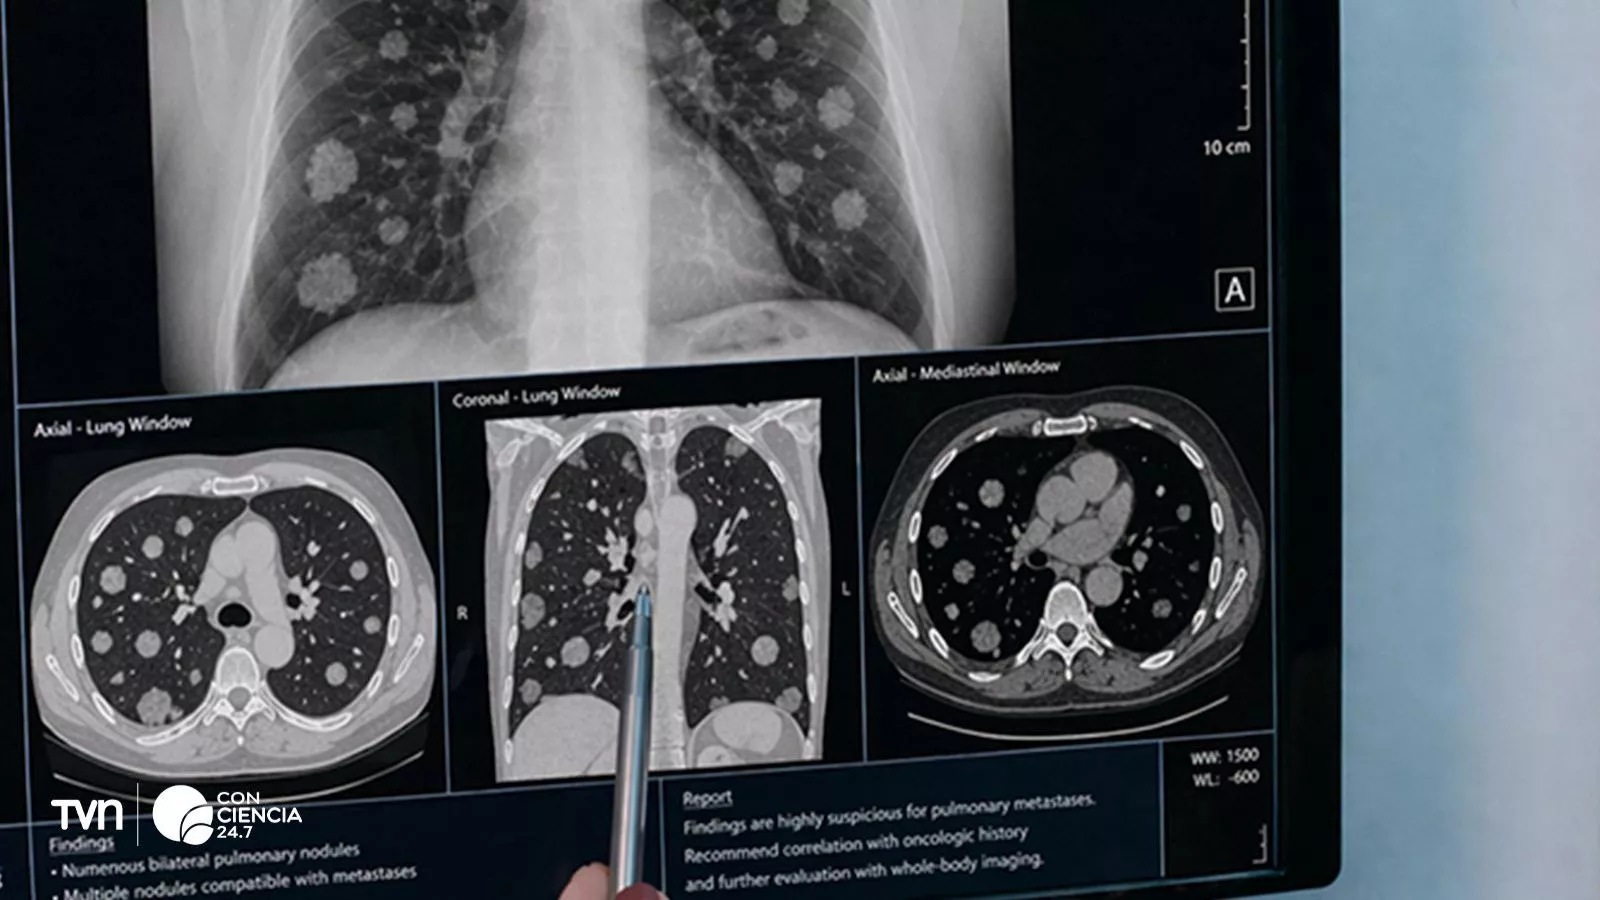

El seguimiento del cáncer implica tareas altamente exigentes, como revisar múltiples imágenes médicas, identificar lesiones y compararlas en el tiempo. Para esto, se utilizan protocolos estandarizados como RECIST 1.1, ampliamente validados en la práctica clínica. Sin embargo, su aplicación sigue siendo manual, demandante y sujeta a variabilidad, lo que abre espacio para errores o diferencias en la interpretación.

El estudio, publicado en la revista Scientific Data bajo el título “A CT Dataset with RECIST Measurements and Comprehensive Segmentation Masks for Tumors and Lymph Nodes”, fue desarrollado por investigadores de la Universidad de Chile y la Universidad de Concepción. La base incluye:

- 1.246 lesiones segmentadas

- 58 tomografías computarizadas

- 22 pacientes con cáncer

- Tumores primarios, metástasis y ganglios linfáticos

- Mediciones clínicas basadas en RECIST 1.1

Se trata del primer conjunto de datos abierto y completo que integra segmentaciones detalladas con seguimiento longitudinal bajo estándares clínicos reales.